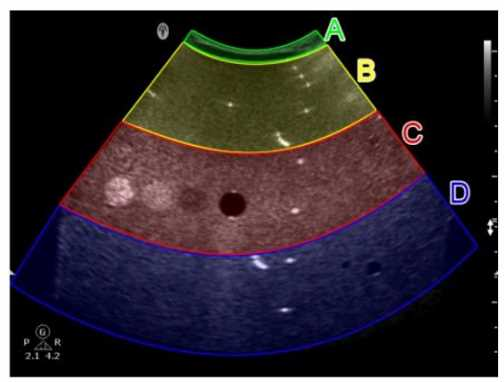

In this image obtained from a tissue-mimicking phantom, which area of the sector is used to evaluate the dead zone?

1. Option A

2. Option B

3. Option C

4. Option D

Answer(s): A

Explanation:

The dead zone in ultrasound imaging refers to the region closest to the transducer where imaging is not possible due to the high amplitude of the initial pulse. In a tissue-mimicking phantom, this is the area where no useful imaging data can be obtained. The purpose of evaluating the dead zone is to ensure that it is as small as possible to maximize the usable imaging depth. In the provided image, Option A represents the area closest to the transducer face, which is typically used to evaluate the dead zone. The other areas are further away and are used for evaluating other parameters such as resolution or depth penetration.

Reference:

American Registry for Diagnostic Medical Sonography (ARDMS) Sonography Principles and Instrumentation guidelines.